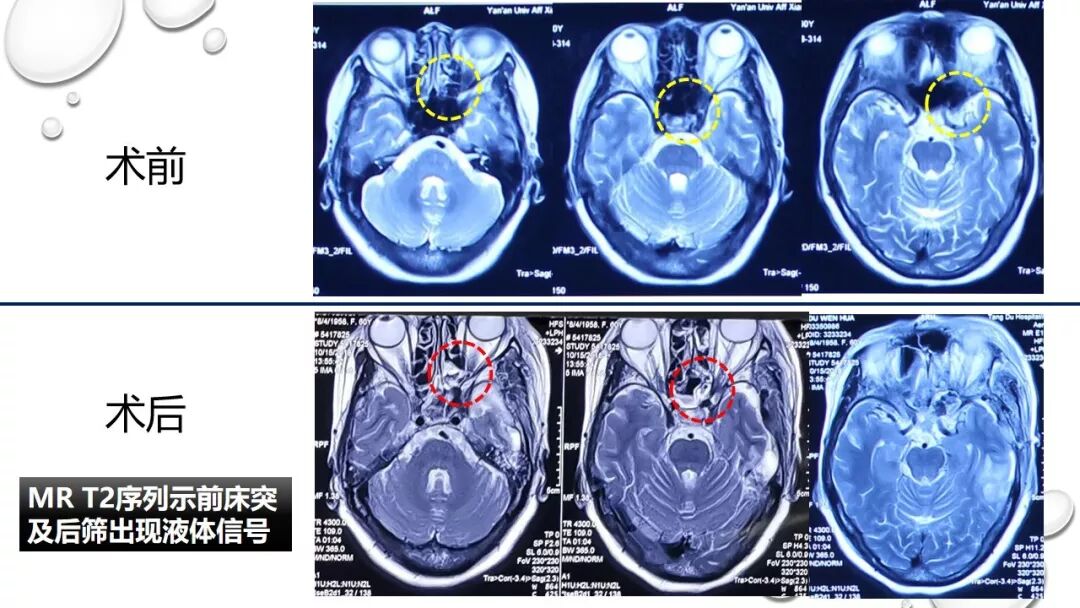

前床突磨除